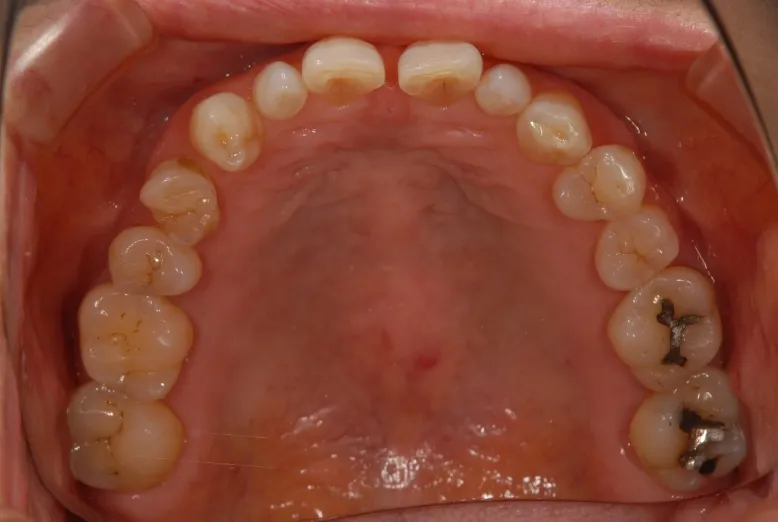

CASE1 60代女性 ダイレクトボンディングによる修復治療

初診

歯石除去で来院されました。

除去後、話を聞くと上顎の前歯の歯と歯の間が離れていることが

以前より気になっていると仰られ、治療計画を立案。

レントゲン写真を撮影。

口腔内写真の撮影

残っている歯の問題点などを解析

さまざまな方向性から、歯のバランスや問題点を解析。

治療計画の立案を行います。